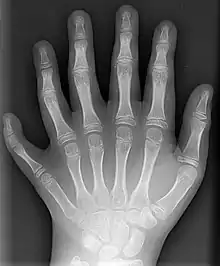

Preaxial polydactyly

This is a less common situation, in which the affectation is on the side of the hand towards the thumb. Radial polydactyly refers to the presence of an extra digit (or extra digits) on the radial side of the hand. It is most frequent in Indian populations and it is the second most common congenital hand disorder. The incidence of radial polydactyly is reported as 1 in every 3,000 live births.[16] The clinical features of radial polydactyly will depend upon the extent of duplication.[14] Radial polydactyly varies from a barely visible radial skin tag to complete duplication. Thumb polydactyly varies from barely visible broadening of the distal phalanx to full duplication of the thumb including the first metacarpal.[17] Radial polydactyly is frequently associated with several syndromes.[18]